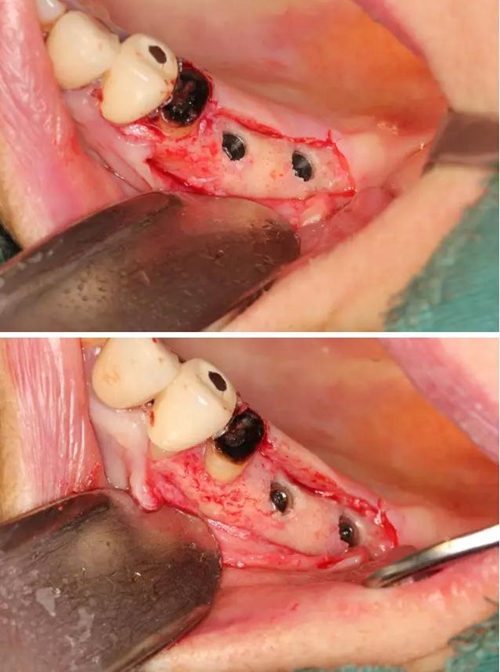

【病例分享】右上內(nèi)提+5冠延長(zhǎng)1 梁光強(qiáng)